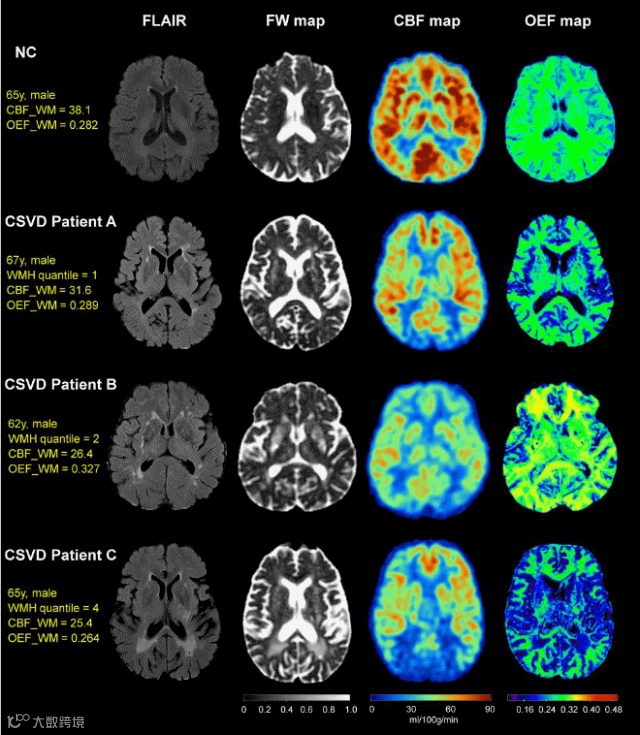

图一:CSVD和NC组的CBF、OEF图

CSVD组的CBF低于NC组;NC组OEF值在各个区域较为一致,而CSVD组脑室周围区域的OEF较低(紫色箭头),脑叶浅表区的OEF稍高(红色圆圈)。

图四:NC和轻、中、重CSVD患者的CBF和OEF图像示例

CSVD患者A、B、C疾病负荷由轻到重,CBF逐渐降低,而OEF则先上升后下降(B患者OEF最高而C患者OEF最低)。